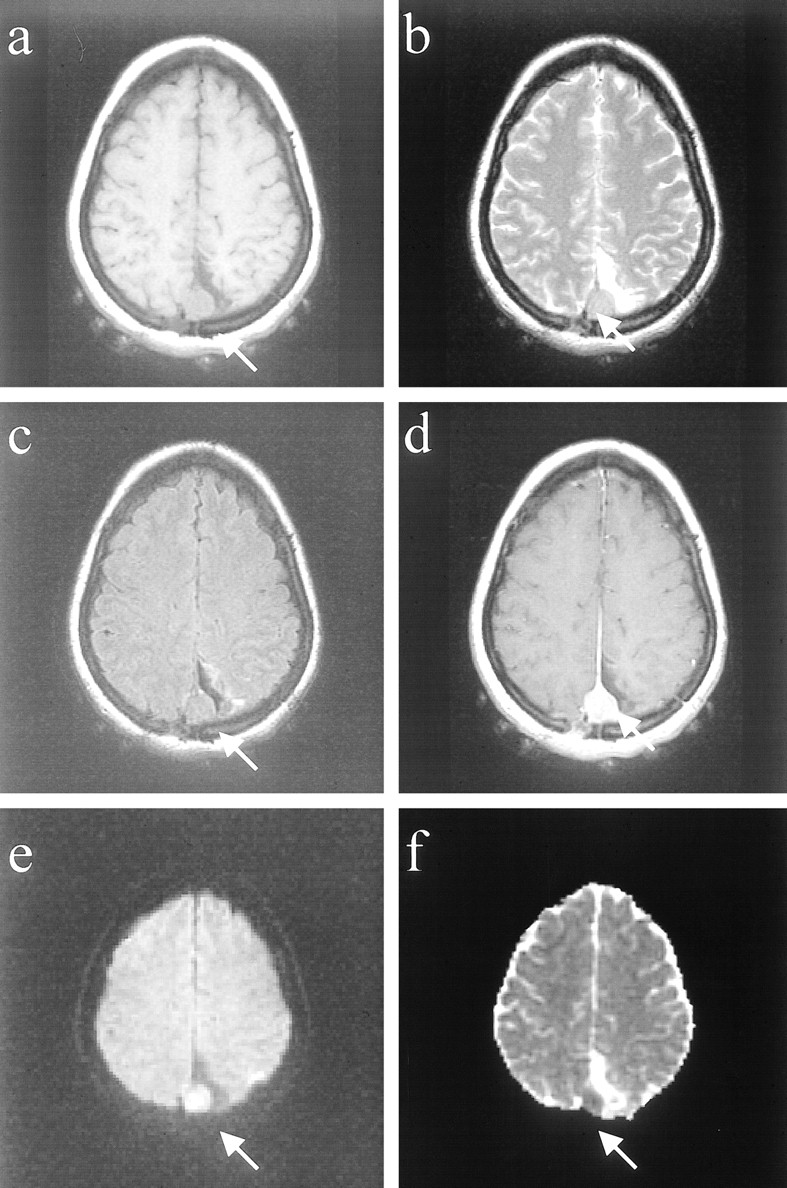

Thirteen (76%) of 17 meningiomas were benign as revealed by histopathologic examination (WHO grade I). On average, these meningiomas had an elevation in the diffusion constant (average, 1.03 ± 0.29 × 10−5cm2/s; range, 0.62−1.80 × 10−5cm2/s) (Fig 2, patient 9). These meningiomas were usually isointense on the short-TR images and predominantly hyperintense on the long-TR images. One of these benign meningiomas, which appeared densely calcified, had a diffusion constant below that of normal brain, overlapping the range of values observed in the malignant and atypical group. The other 12 meningiomas had diffusion constant values higher than that of normal brain, and none of these were densely calcified.

Images of a patient (patient 9 in the Table) with a benign meningioma (WHO grade I).

A, Axial T1-weighted image of right temporal meningioma with “pseudocapsule” sign.

B, Axial fast spin-echo T2-weighted image shows that the mass is slightly hyperintense to cortex.

C, Fast fluid-attenuated inversion recovery image shows mass to be hyperintense to cortex.

D, Contrast-enhanced T1-weighted image shows intense, homogeneous enhancement.

E, Mass is predominantly isointense/slightly hyperintense on the diffusion-weighted image.

F, On the ADC map, the mass appears isointense/hyperintense to cortex, with a diffusion constant value (0.93 × 10−5 cm2/s) that is slightly elevated compared with normal brain parenchyma.